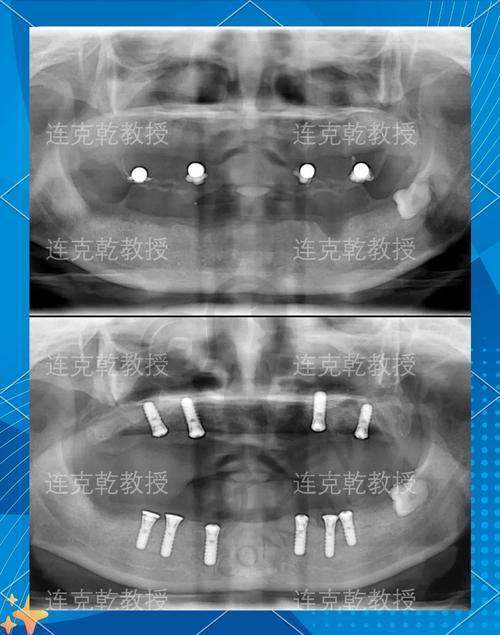

第一次来到成都贝臣口腔医院,给我的第一印象就是环境整洁、舒适,医护人员的态度也非常热情。我挂了号之后,特别快就见到了医生。医生首先详细地询问了我的牙齿病史、目前的症状以及我的期望。然后,安排我进行了一系列的口腔检查,包括口腔X光片、CT扫描等。这些检查非常全方面,让医生能够正确地了解我的口腔状况,包括牙槽骨的密度、高度、宽度等。

成都贝臣口腔医院的全口牙齿种植技术有特别多特色之处。首先,医院采用的是精良的数字化种植技术。通过口腔CT扫描等设备,医生可以严谨地获取患者口腔的三维数据,然后利用计算机软件进行模拟种植,制定出更适合患者的种植方案。这样可以大大提高种植的正确性和成功几率。